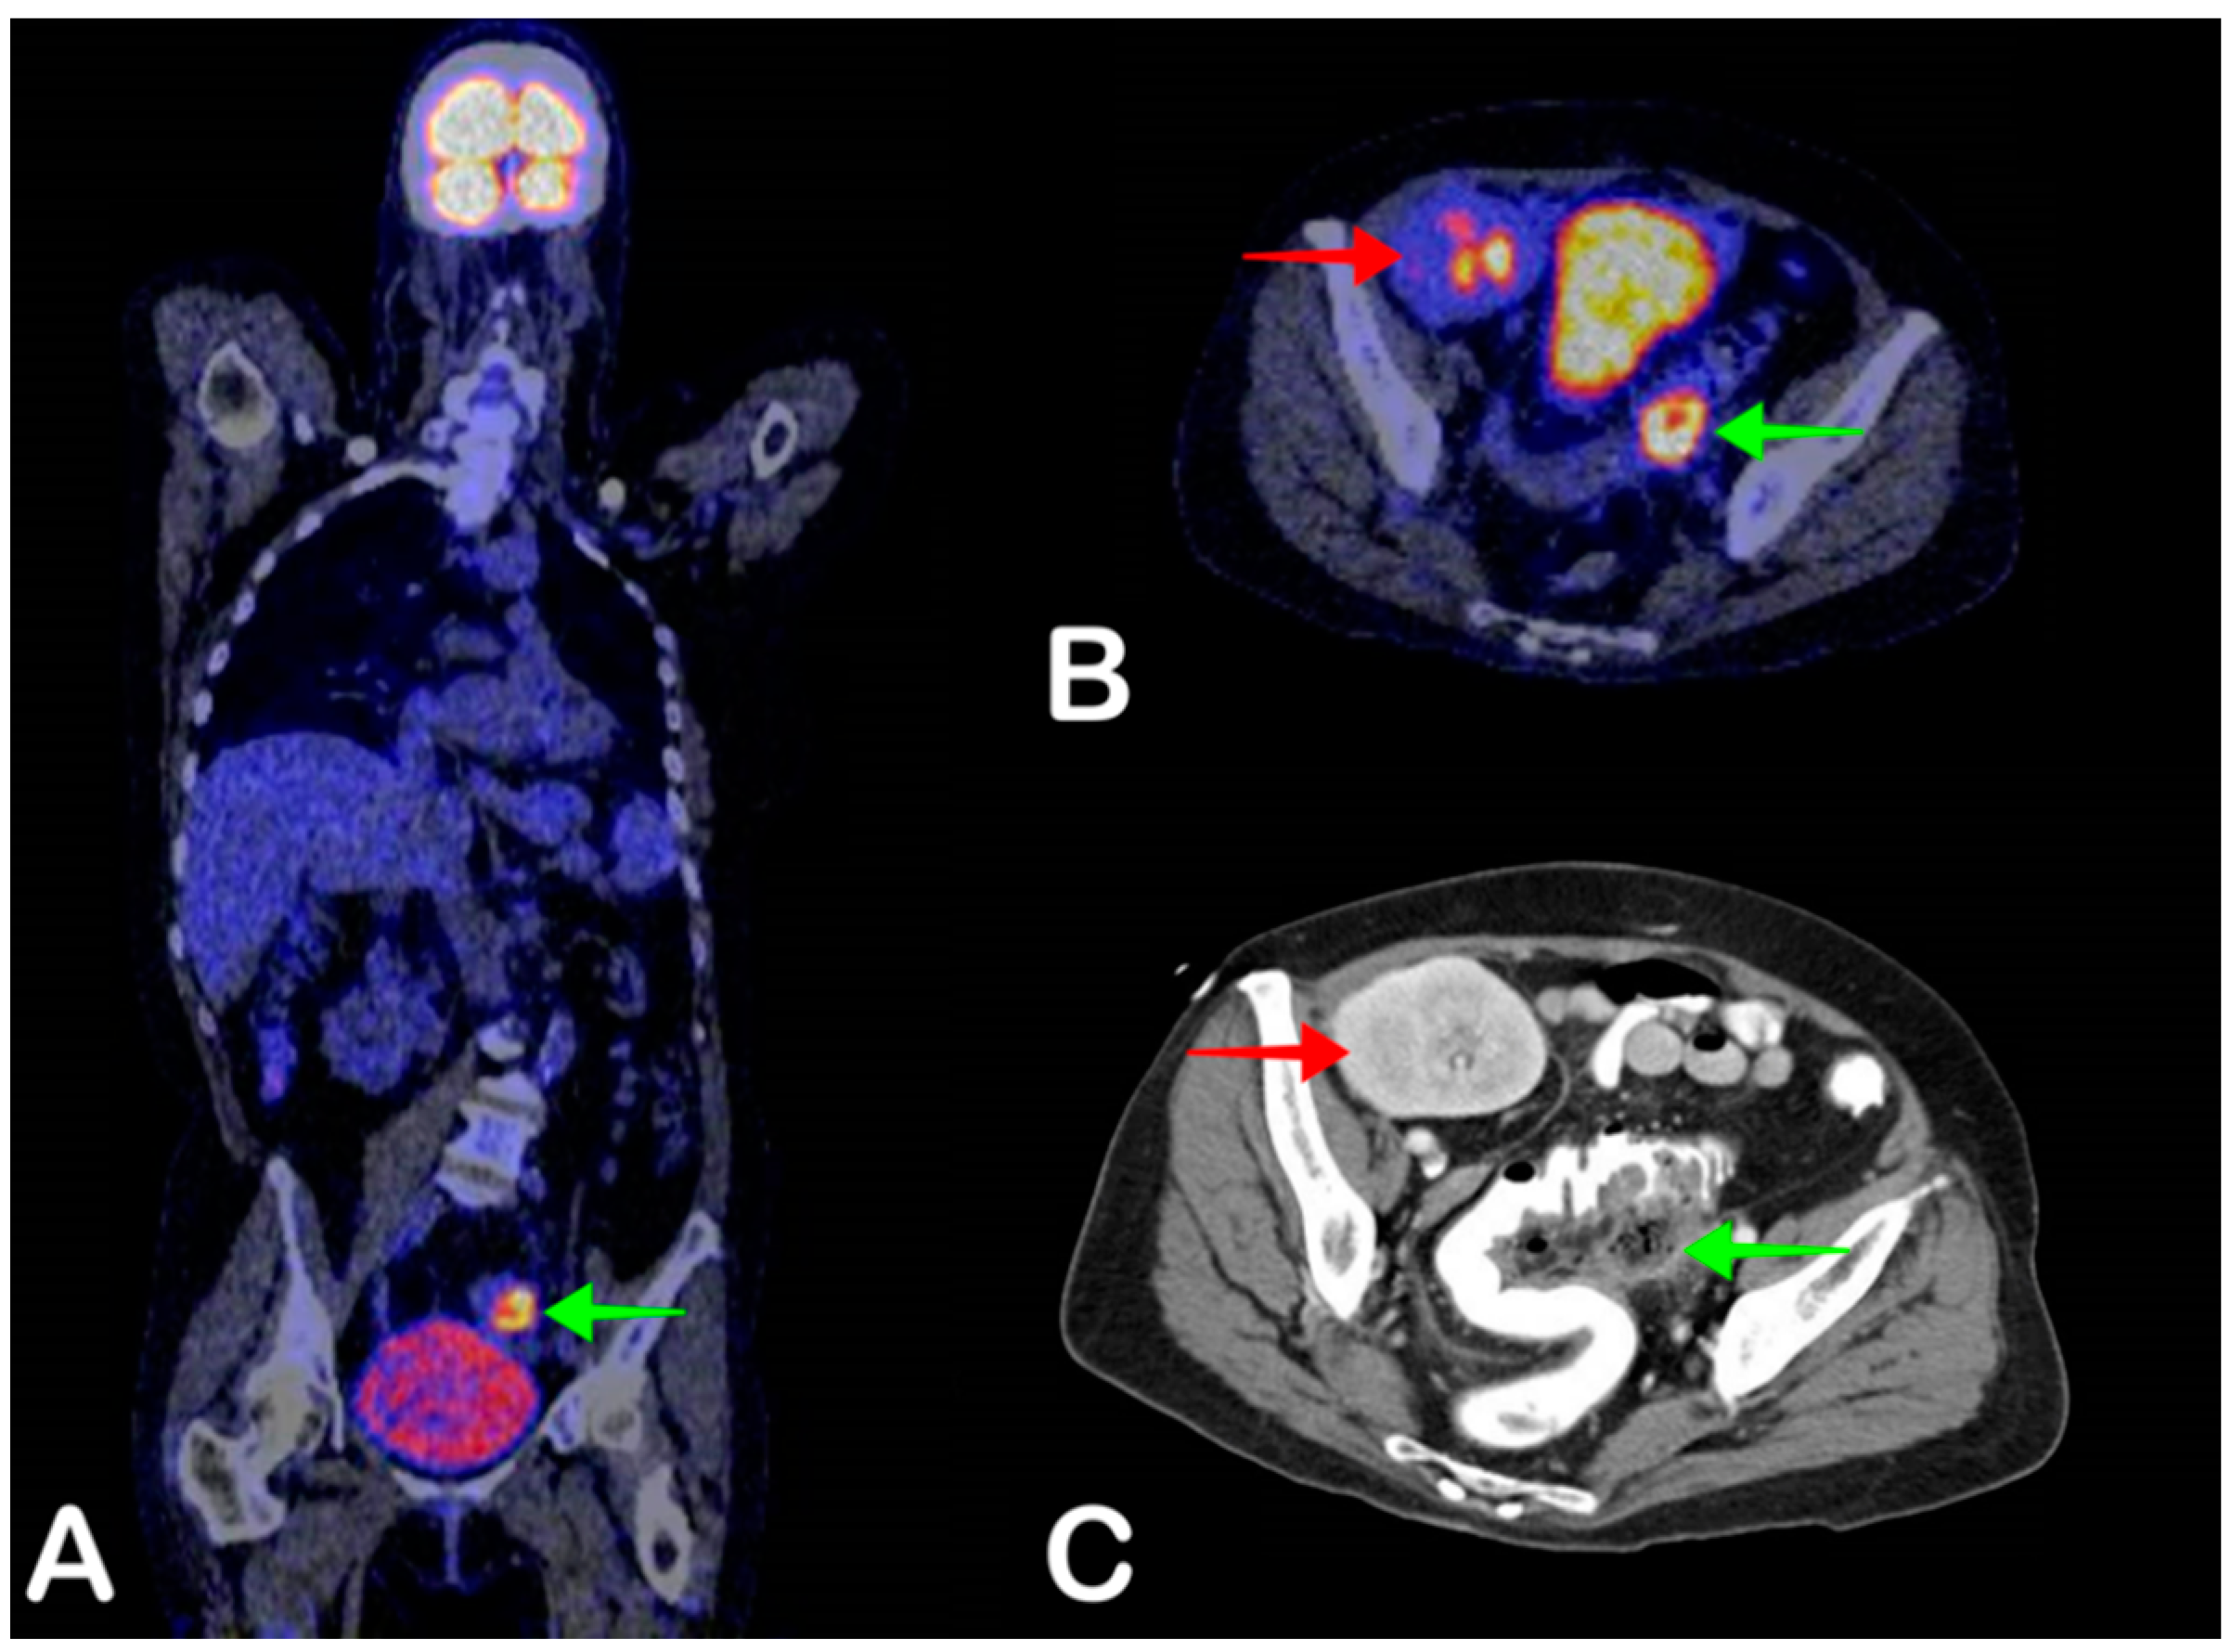

2.6. Cyst Infection

- Pijl, J.P.; Glaudemans, A.W.; Slart, R.H.; Kwee, T.C. 18F-FDG PET/CT in Autosomal Dominant Polycystic Kidney Disease Patients with Suspected Cyst Infection. J. Nucl. Med. 2018, 59, 1734–1741. [Google Scholar] [CrossRef] [Green Version]